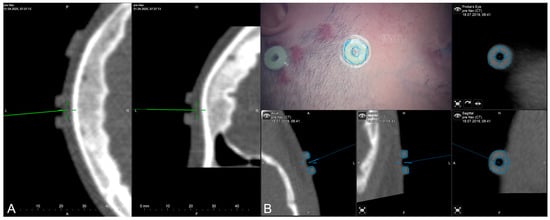

The applicability of navigation and microscope-based AR support during the surgical procedure and educational purposes tremendously depends on the navigational accuracy. The presented setup allowed for different methods to gain, keep, and restore navigation accuracy throughout the procedure. In the recent setup, automatic intraoperative CT-based registration is used for mapping of image and patient data showing a high registration accuracy with very low TREs estimated using artificial landmarks. Navigation accuracy can be verified and quantified in different ways throughout the procedure, e.g., using artificial landmarks not used for the registration procedure assessed with a pointer (see Figure 3A) or using microscope-based AR with segmented outlines of the landmarks (see Figure 3B).

Figure 3. Accuracy checks using artificial landmarks either assessed with a pointer (A) or the virtualized pointer using the operative microscope (B) with segmented outlines of the artificial marker visualized in the operating field using microscope-based AR.

Furthermore, during the surgical procedure, AR can also be utilized for accuracy checks and navigation updates to reassure high navigational accuracy throughout the intervention using anatomical landmarks, such as cortical vascular structures eligible for in-plane (2D, no depth inaccuracies) corrections of spatial inaccuracies (for further details see [41]) as well as 3D reconstruction of the cortical profile (see Figure 4).

Figure 4. Accuracy checks using a 3D reconstruction of the cortical profile with the microscope’s focal plane being stepwise moved along the viewing trajectory.